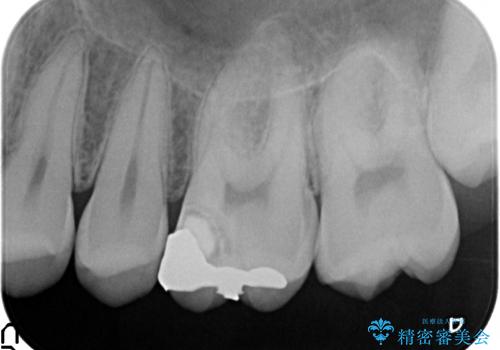

- 3日ほど前から何もしなくても左上奥歯がズキズキ痛むので診て欲しいといらっしゃった方の症例です。

検査の結果左上6に持続痛を認めたため根管治療を行い、症状の緩解を確認後オールセラミッククラウンによる補綴を行いました。